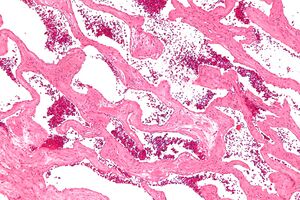

Micrograph of a cavernous liver hemangioma. H&E stain. | |